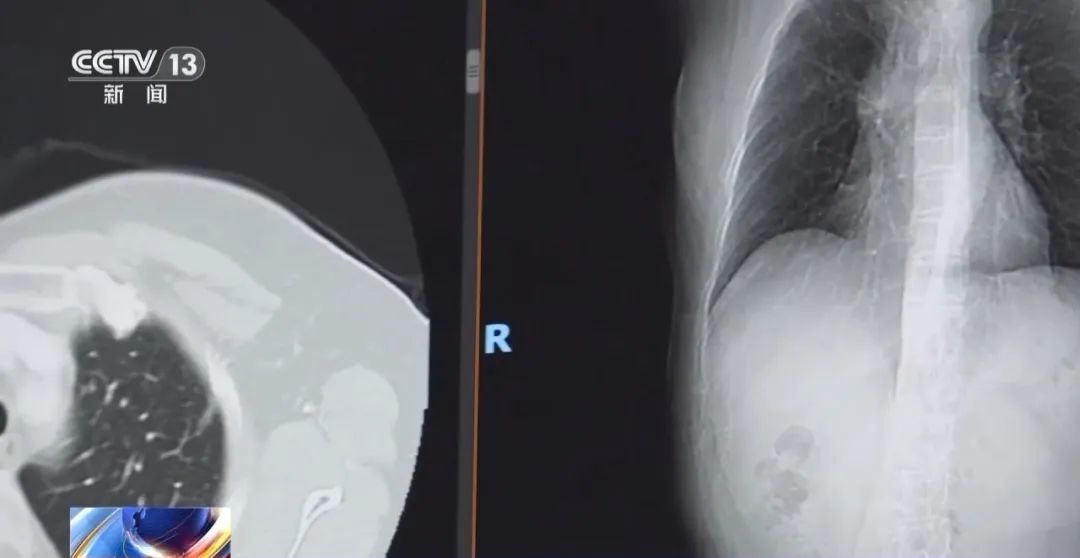

在宁波山区,80多岁的陈阿婆(化姓)一直过着简单而健康的生活:平时做做农活、干干家务,不沾烟酒、远离工业污染……然而,一次体检打破了平静——胸部CT显示陈阿婆左肺有磨玻璃结节,术后确诊为肺腺癌。

北京大学肿瘤医院胸外一科主任 陈克能:对那些非高危的人群,即便是低剂量螺旋CT看见了小结节,我们也要分如下的情况,如果是一个纯磨玻璃样结节,简单说没有实性成分,就不要过度惊慌;如果结节位置不在胸膜下,又不在叶间裂,这些大可不必紧张,没有必要每一年做一次CT。

专家表示,对大多数筛查发现的磨玻璃样小结节要谨慎解读,它生长得非常缓慢,可以给它一定的冷静期进行观察,不建议过度治疗。

随着我国医学进步,肺癌患者的治疗有明显突破,磨玻璃样结节的肺癌,5~10年的生存率接近百分之百,实性肿块一期肺癌的5年生存率约为70%~80%。